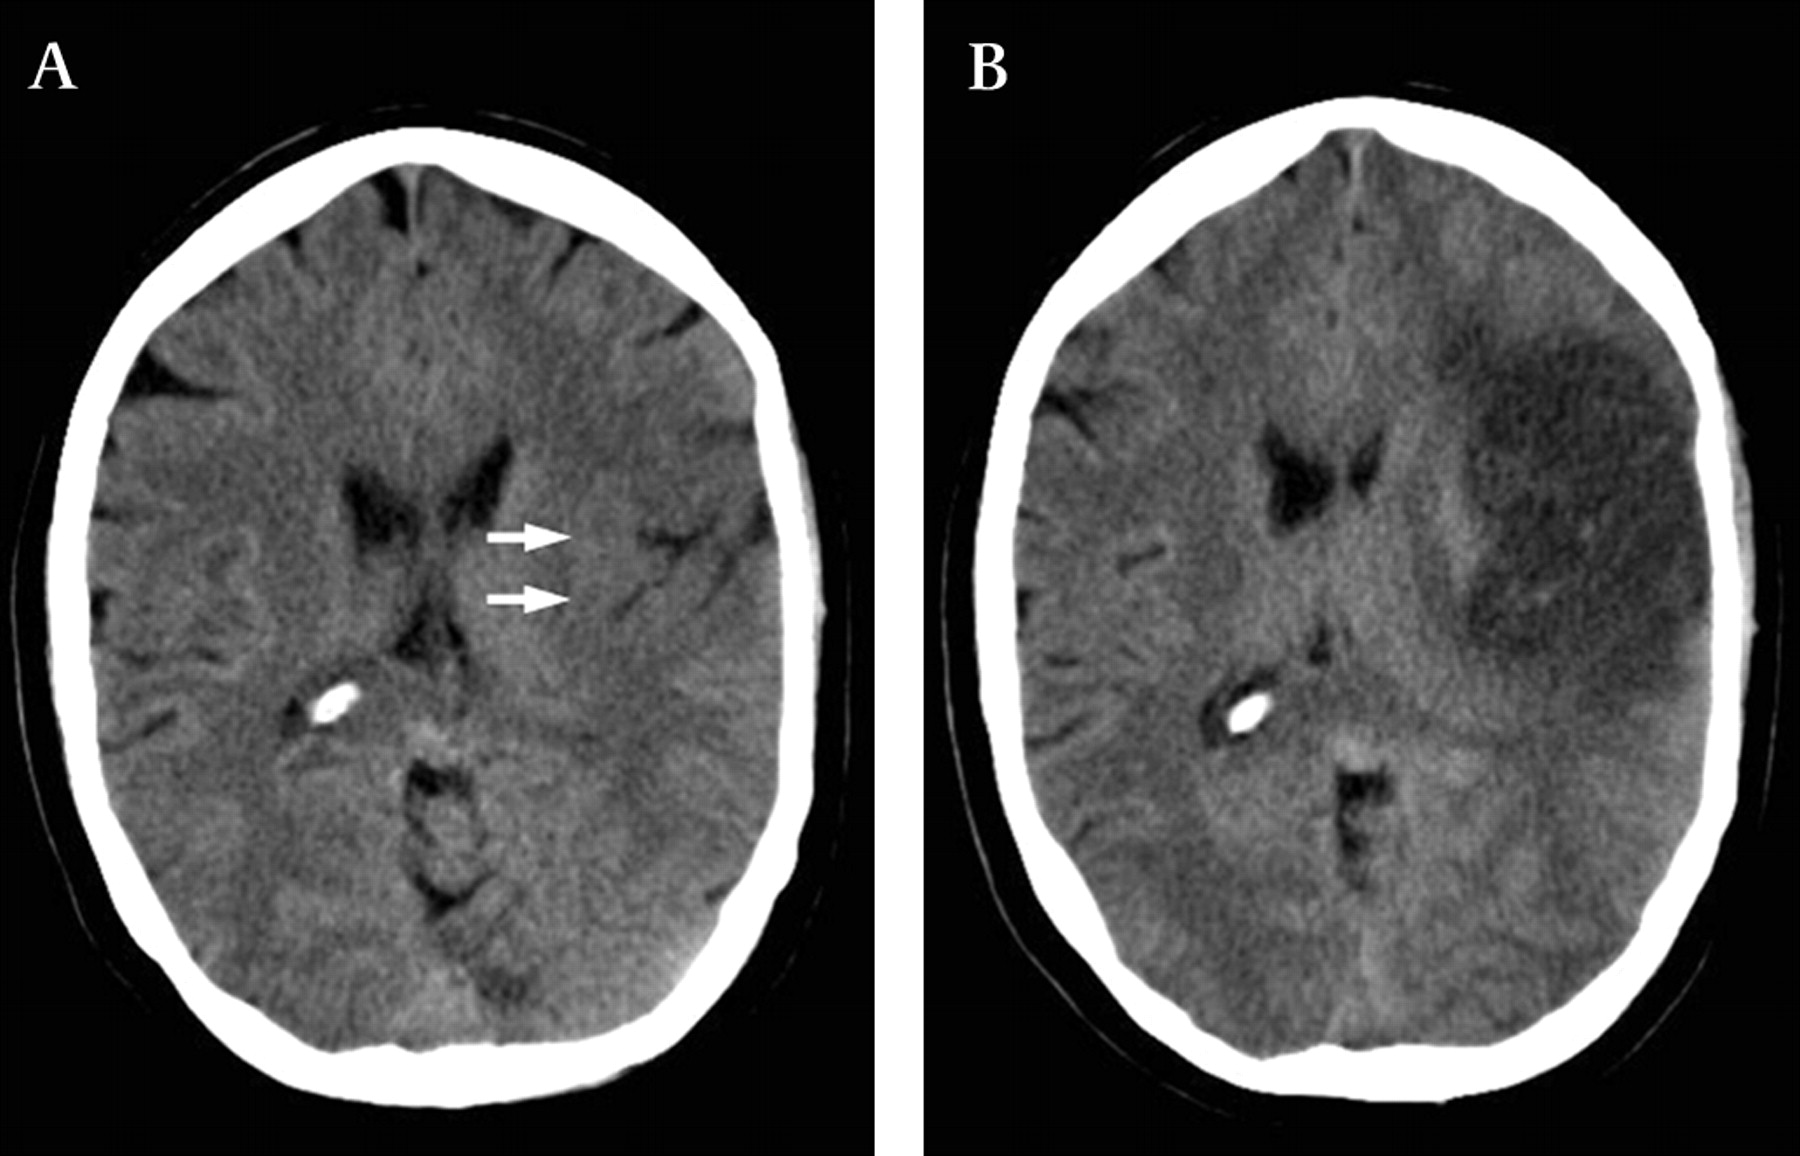

1. 신속한 평가 및 진단: 뇌경색 초기증상과 징후를 신속하게 인식하는 것은 적시에 개입하고 환자 결과를 개선하는 데 필수적입니다. 의료 전문가는 NIHSS(National Institutes of Health Stroke Scale)와 같은 도구를 사용하여 잠재적인 뇌경색 환자를 신속하게 평가하고 컴퓨터 단층 촬영(CT) 스캔 또는 자기 공명 영상(MRI)을 포함한 진단 테스트를 시작하여 진단을 확인하고 유형을 결정해야 합니다.